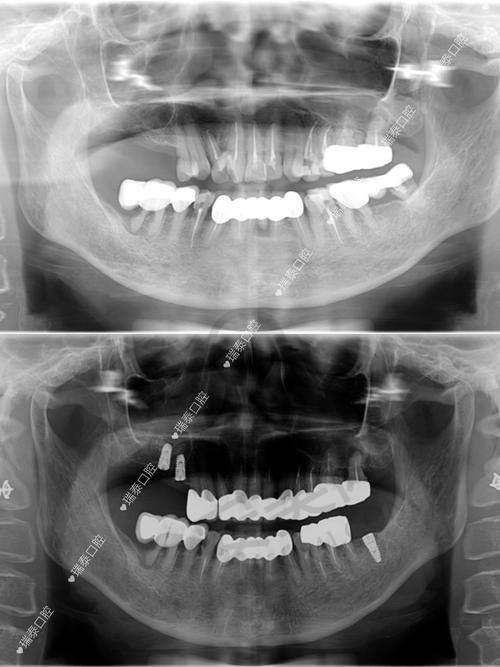

对于全口种植,这是一项比较复杂的种植项目,需要医生有较高的技术水平和丰富的经验。王弄医生凭借自己多年的临床经验和不断学习提升的技术,能够根据患者的口腔骨骼情况、咬合关系等因素,制定出个性化的全口种植方案。在种植过程中,他能精细地把握种植体的植入位置和角度,确保种植体与口腔组织的良好结合,为患者修复全口牙齿的功能和美观。

在常规种植方面,王弄医生也有着自己的优势。他会利用数字化设备进行术前评估和方案设计,使种植过程更加精细。而且他的微创种植技术,能让手术创口更小,减少患者的痛苦和术后肿胀的情况。就像有患者缺牙五年不敢种,王弄医生为其设计小创口方案,术后几乎没肿,现在啃排骨都没问题。

对于复杂牙列缺损缺失种植修复,王弄医生更是有着丰富的应对经验。他能够处理各种复杂的口腔情况,如骨量不足等问题。他会采用复杂软硬组织重建手术等方法,为种植创造良好的条件,然后进行种植修复,让患者重新拥有健康的牙齿。